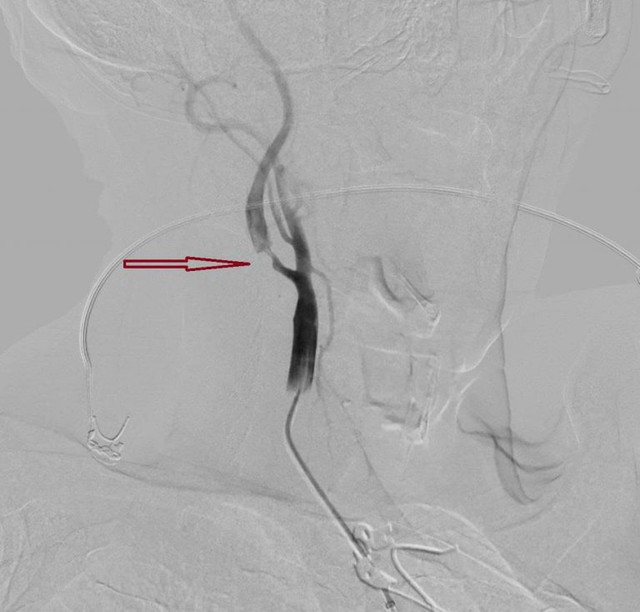

Hình DSA cho thấy hẹp nặng đoạn gốc động mạch cảnh trong ngoài sọ trước can thiệp của bệnh nhân đột quỵ. Ảnh: BVCC

Trước tình thế nguy cấp, từng giây phút đều quý giá để bảo vệ các tế bào não và tính mạng cho bệnh nhân, bác sĩ khoa Sọ não cột sống 2 cũng được huy động kịp thời. Song song đó, kết quả chụp CTA ghi nhận ông bị tắc động mạch não giữa M1 bên phải – một động mạch lớn, và hẹp nặng động mạch cảnh trong bên phải đoạn gốc.